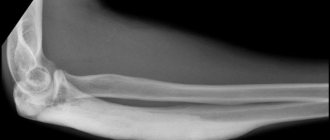

Osteosclerosis is a condition - a symptom of many diseases - consisting of thickening of one or more